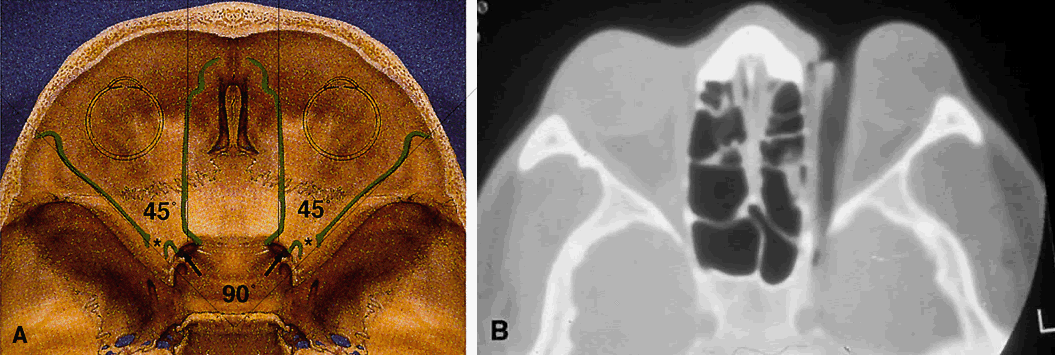

The lesser wing of the sphenoid bone is initially cartilaginous, but the greater wing and the rest of the orbital bones are membranous in nature and ossify and fuse between the 6th and 7th months of gestation. As the orbital bones develop, the eyes converge from an initial 180° relation to their final position of 68°, achieved in infancy. However, the orbital axis remains somewhat divergent at birth (115° between the lateral orbital wall and the skull axis) when compared with that of adults (45°) (Fig. 4).15

Fig. 4. Angular separation of the globes at 2 months' gestation, 3 months' gestation, birth, and adulthood. (Fries PD, Katowitz JA: Congenital craniofacial anomalies of ophthalmic importance. Surv Ophthalmol 35:87, 1990)

Fig. 11. Osteology. A. An axial view of the orbital roof demonstrates the parallel course of the medial orbital walls (green). The lateral orbital walls (green) lie at an angle of 90° from each other, or 45° from each medial wall. Remember that the superior orbital fissure, and not the medially placed optic canal, lies at the posterior aspect of the orbit. B. CT of a wooden foreign body within the orbit after trauma. Note that the tip has traveled through the superior orbital fissure and lies within the CS, not the optic canal. In this case, the greatest worry was not the patient's vision, but the possibility of lacerating injury of the carotid siphon, which was confirmed on subsequent arteriography (A modified from Zide BM, Jelks GW: Surgical Anatomy of the Orbit, p 9. New York, Raven Press, 1985. B courtesy John W. Shore, MD, Austin, TX)